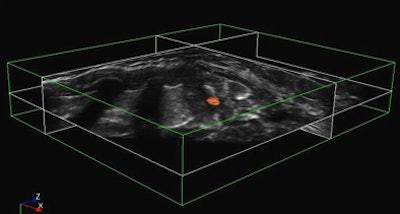

| Two kinds of feature parameters, identified as "mean" and "stick," are extracted to generate the membership function for fuzzy reasoning. Below, the initial results of fuzzy tumor detection show tumor regions in black, boundary regions in gray, and normal tissue in white. Next, graphical user interface demonstrates final CAD results after application of five tumor criteria (size, mean value, long-short ratio, volume ratio, standard deviation) to filter out nontumors. Bottom image shows final view of CAD-detected tumor in orange. |

![]() |

Among the 45 datasets, 64 lesions (28 benign and 36 malignant) were identified. The experimental CAD scheme's accuracy for tumor detection was 78.60% for benign lesions and 91.70% for malignant tumors.

"The sensitivity is up to 85.9% [55/64] with a 1.71 false-positive rate per case," Chang said. "We can check each slice in about two to three minutes."